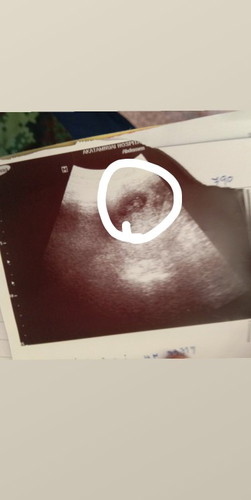

รุปนี้อัตราซาวตอนยังไม่ถึง10สัปดาห์ใช่น้องไหมค้ะ